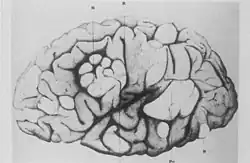

- El neurólogo francés Désiré-Magloire Bourneville tuvo un encuentro fortuito con la enfermedad que llevaría su nombre. Trabajaba como asistente no oficial de Jean Martin Charcot en La Salpêtrière.[10] Mientras sustituía a su maestro, Louis J.F. Delasiauve,[12] atendió a Marie, una niña de 15 años con retraso psicomotor, epilepsia y una «erupción vascular-papulosa confluyente en la nariz, las mejillas y la frente». Tenía antecedentes de convulsiones desde la infancia y fue llevada al hospital infantil a los tres años y declarada un caso sin esperanza. Tenía dificultades de aprendizaje y no podía ni caminar ni hablar. Mientras estaba bajo el cuidado de Bourneville, Marie tuvo un número cada vez mayor de convulsiones, que venían en racimos. Fue tratada con quinina, bromuro de alcanfor, nitrito de amilo y la aplicación de sanguijuelas detrás de las orejas. El 7 de mayo de 1879, Marie murió en su cama del hospital. La autopsia reveló tubérculos duros y densos en las circunvoluciones cerebrales, que Bourneville llamó Sclérose tubéreuse des circonvolutions cérébrales («esclerosis tuberosa de las circunvoluciones cerebrales»). Concluyó que eran la fuente (foco) de sus convulsiones. Además, se encontraron masas duras y blanquecinas, una «del tamaño de una nuez», en ambos riñones.[13]